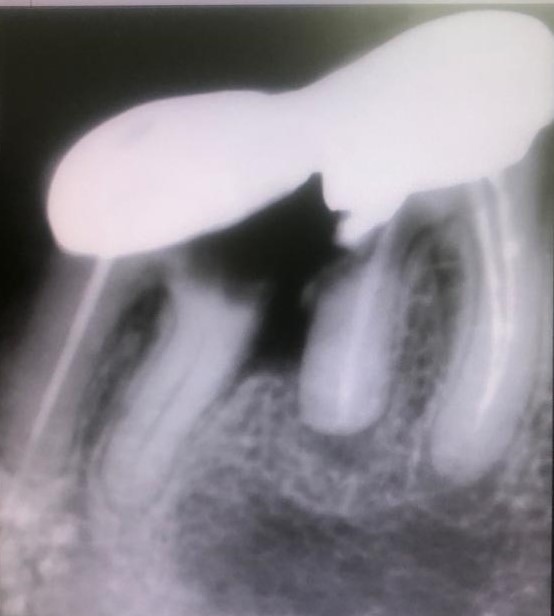

Presentamos un nuevo caso en el que la paciente presenta un gran dolor en su prótesis antigua (15 años) sobre dientes naturales tallados en zona inferior de molares. Es una paciente muy bruxómana, se unieron dos molares tallados con dos coronas. En el caso que presentamos el molar anterior estaba endodonciado ya antes de colocar la prótesis fija, pero el molar distal no. Y éste era la causa del gran dolor. Esto es por haberse filtrado creando caries y destrucción dentaria que llegaba al nervio. En conclusión, produciendo una gran pulpitis.

Esto provocaba en la paciente un gran dolor, pero ella no contemplaba en ese momento la opción de levantar la prótesis para explorar las piezas que había debajo, poder visualizar la destrucción dental y rehacer todo con una prótesis nueva. Por tanto, para quitar el dolor normalmente habría que haber hecho las extracciones de los dos molares, lo cual sería muy invalidante. En la clínica decidimos hacer una endodoncia de la raíz distal del último molar a través de la prótesis por la zona oclusal, y hacer odontosecciones de las raíces lesionadas sin quitar la prótesis. Ésta va permanecer tal como estaba.

Lo cierto es que las raíces  ya estaban bastante separadas de el resto de los molares correspondientes por su destrucción, lo que nos permitió la extracción de estas raíces en concreto. Teniendo en cuenta también que las raíces mesial y distal de cada molar no estaban unidas entre sí, sino que había una separación entre ellas.

La técnica quirúrgica para este menester es parecida a una apicectomía, pero en lugar de quitar solo el ápice radicular quitamos toda la raíz dental. Así pues lo que se hizo fue extracción de la raíz distal del primer molar y extracción de la raíz mesial del segundo molar. Con lo que la prótesis sigue teniendo dos pilares.

En conclusión, lo que hicimos fue alisar la prótesis por debajo de forma que quede higiénica y por tanto no retenga restos. La técnica quirúrgica quedo muy bien. El tiempo de inflamación de la cara es como si se hubiera hecho la extracción de la muela del juicio, pero una vez se va la inflamación el paciente sigue haciendo vida normal, como el día que se le puso la prótesis.

Con la secuencia de imágenes se comprende muy bien la técnica quirúrgica realizada.